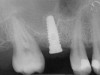

A 53-year-old female was referred for evaluation of a fracture of tooth No. 24. The tooth had been treated endodontically 5 years prior. The radiograph revealed a complete fracture of the tooth involving the crown (Figure 12). Tooth extraction and immediate placement of a an implant that was 10 mm in length and 3.75 in diameter was planned.

At the time of surgery, the tooth was extracted without harvesting any mucosal flap because the implant site was prepared by means of a pilot drill bur (Figure 13) and alternating osteotomes (Figure 14A and Figure 14B). The implant was positioned and showed primary stability. The implant was loaded 2 days after surgery. Then, splinted PFM crowns supported by custom gold abutments were delivered. At 6 months posttreatment, the radiograph revealed no bone resorption and the clinical result was optimal (Figure 15A and Figure 15B).

Figure 12 Preoperative radiograph shows fractured tooth No. 24.

Figure 15B Posttreatment radiograph, 6 months after the initial surgery.